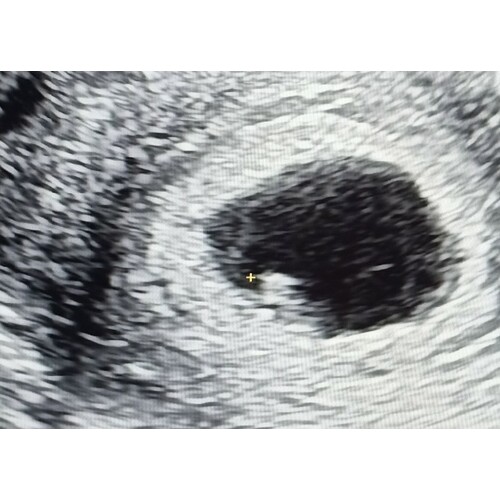

Heyhey ik heb afgelopen woensdag echo gehad omdat ik zoveel pijn in mijn buik had. Was toen 5+5.. bij mij was er alleen een vruchtzakje te zien. Niet eens een dooierzakje of vruchtje.

Ze zei hier dat het opzich voor dat termijn heel normaal is. Hier zelf ook 0.0 bloed verloren. En echt wel zwangerschapssymptomen. Vanochtend omdat ik mij zo druk maakte nog een test gedaan en die gaf 3+ aan. Niet eerder gehad. Dus zal wel goed zitten denk. Ik heb de 15e een pretecho gepland staan.. omdat ik toch even eerder wil als 26mei..

Ik heb vandaag mijn eerste inwendige echo gehad bij de gynaecoloog. Volgens mijn berekening nu 6 weken zwanger.

Op de echo was een dooier zakje te zien maar geen vrucht.

Gynaecoloog vertelde dat dit nu 2 dingen kon betekenen: of te vroeg of vruchtje word afgestoten en resulteert dadelijk in een miskraam. Ik moet volgende week vrijdag weer nieuwe inwendige echo laten maken.

Ik had een echo bij bijna 6 weken en daar was hetzelfde te zien. Bij de tweede echo met 7+4 was een mooi kloppend hartje te zien, dus het kan zeker ook gewoon goed gaan! Ik heb nog twee echo's gepland staan bij 10+3 en bij 11+4 dus ik hoop dat alles dan allemaal goed is 馃檶馃徏

Ik ben onverwachts zwanger. 3 mei positief getest en omdat ik geen cyclus weet ivm pil gebruik afgelopen vrijdag echo. Alleen vruchtzak en dooierzak te zien dus de 26e terug. Ze ging uit van een nog te prille zwangerschap.